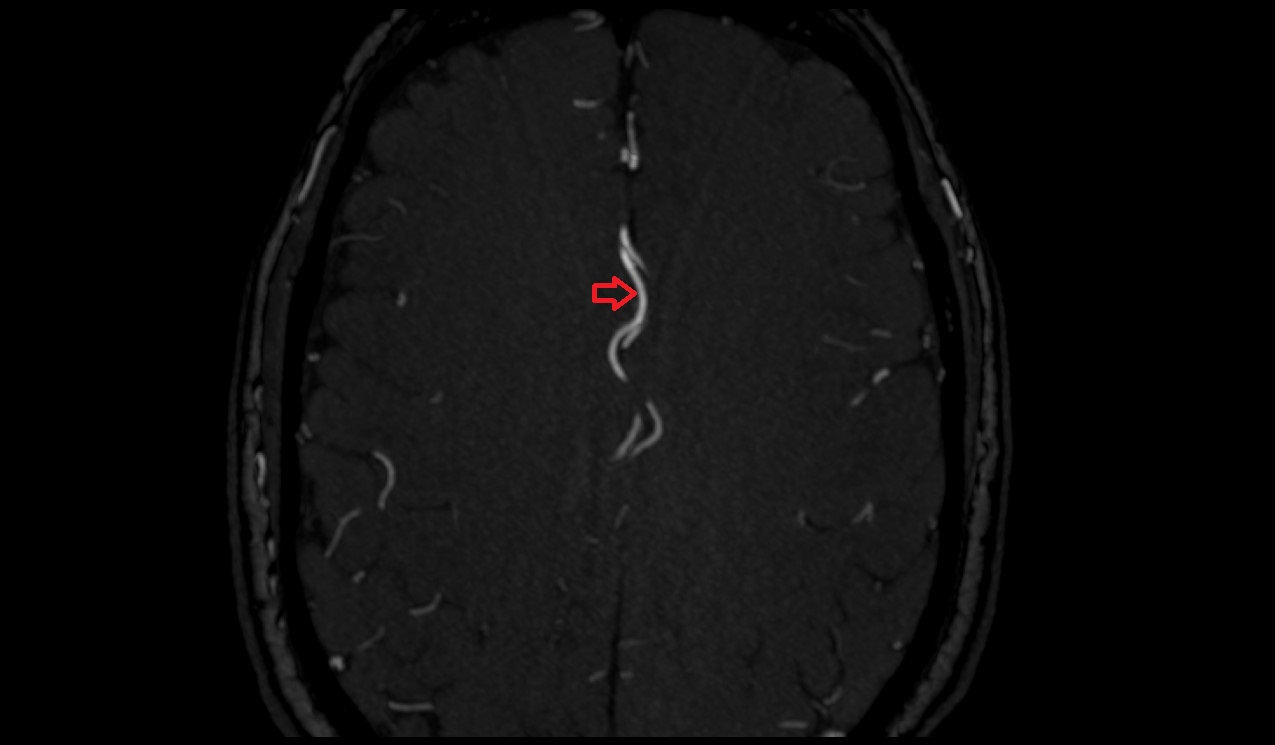

- Long medial striate artery